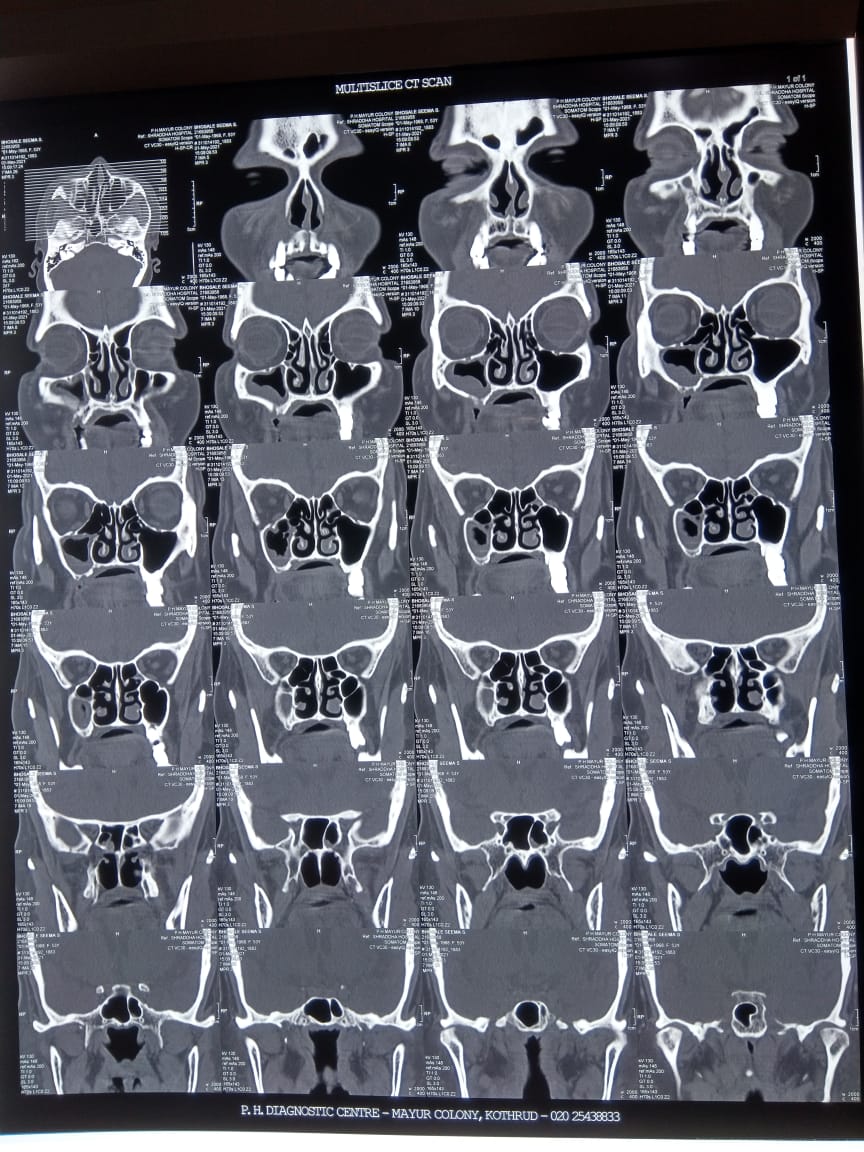

एक महिन्यां पुर्वीच करोना संसंर्ग होऊन बऱ्या झालेल्या महिला रुग्णाला ह्या काळ्या बुरशीची म्हणजेच म्युकोरमायकोसिस ची लागण झालेली. ती महिला डेक्कन हर्डीकर हाॅस्पीटल येथे दाखल झाली. सर्व तपासण्या जसा की तोंडाचा सायन्सचा एक्सरे, स्कॅन, योग्य ती दाताची तपासणी करण्यात आली व रुग्णाला काळी बुरशीचा आजार असल्याचे स्पष्ट झाले.